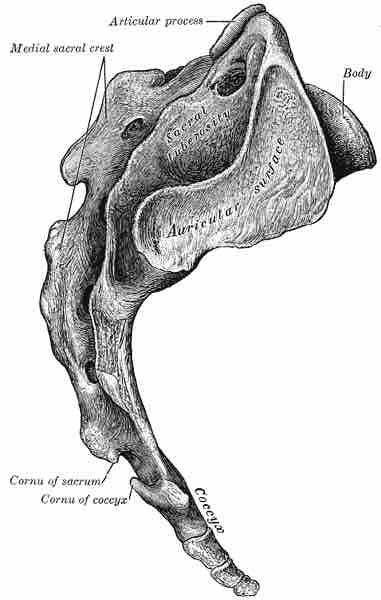

Regional Vertebral Characteristics

Coccyx

Lateral view of coccyx shown beneath the sacrum.

This is a drawing of a coccyx, shown from beneath the sacrum so its tail-like form is displayed.